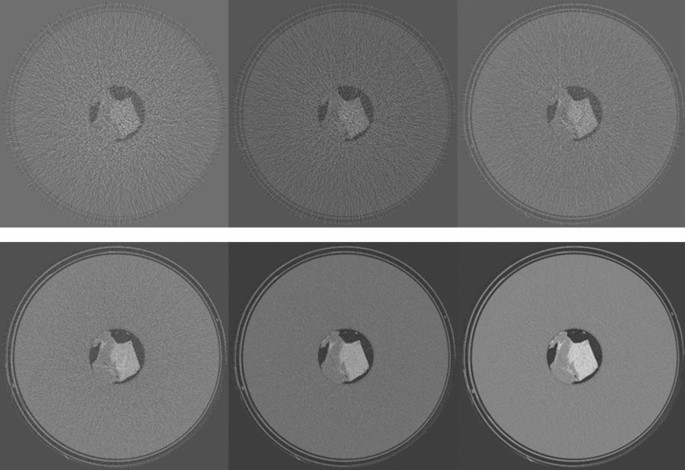

For the T1 tissue sample, the dependence of CNR on MGD was evaluated at 22 keV. Images were acquired at 0.125, 0.25, 0.5, 1, 2, 5 and 20 mGy. CNR was evaluated always on the same ROIs, which were accurately selected in order to avoid ring artifacts (see Fig. 8), which would have altered the estimation of CNR. In Fig. S4 in the Supplementary Materials, the CNR (left panel) and the percentage of zero-counting pixels (right panel) are reported as a function of dose. The dose for each acquisition, the corresponding fluence rate in input to the sample in unit of (photons/mm2/projection), the measured Nmin, the percentage of zero-counting pixels and the CNR are reported in Table S1 (Supplementary Materials). CNR shows a behavior proportional to the square root of Nmin down to 2 mGy (~ one count/pixel). For doses below 1 mGy, the CNR slightly increases with the decrease of Nmin. This effect is not realistic and it is due to the removal of the zero counting pixels. Actually, the preprocessing procedure induces an increasing smoothing in the processed images with the increase of the number of the removed zero counts, thus improving the CNR44.

In Fig. 8, the reconstructed slices on which CNR was calculated are shown, for different doses. At 20 mGy, the tissue is perfectly reconstructed, although a small ring artifact is visible close to the center of rotation. This artifact is due to a non-perfect equalization of two adjacent detector modules. At 5 mGy ring artifacts of the same nature, corresponding to the junctions of other detector modules, are visible, but the quality of the image is still very good. Below 2 mGy the ring artifacts start to significantly alter the image quality. Below 1 mGy, effects due to the photon starvation start to become dominant and image details are rapidly lost. This is also appreciable considering CNR in Fig. S4 and Table S1 (Supplementary Materials): below 1 mGy CNR is completely dominated by artifacts and no more represents actual contrast in the image.